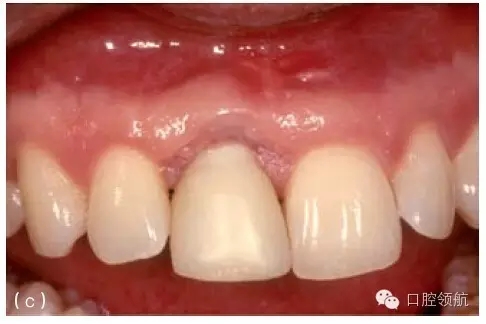

第二種方法是拆除冠和基臺(tái)后行軟組織移植,軟組織瓣冠向復(fù)位部分或完全覆蓋種植體(圖8.23a~e)。愈合后,可能需要二期手術(shù)重新連接基臺(tái)和冠。該方法的優(yōu)點(diǎn)如下:

圖8.23 (a)右上頜側(cè)切牙(7號(hào)位點(diǎn))種植體和冠初診時(shí)情況。約有3mm的黏膜退縮,種植體金屬領(lǐng)圈暴露。(b)第一步,拆下冠和基臺(tái),讓種植體2周時(shí)間的自然愈合。(c)做半厚瓣翻瓣,結(jié)締組織移植至種植體并進(jìn)行瓣的冠向復(fù)位。面觀顯示4周的愈合期后種植體完全埋在黏膜下。(d)做小切口,足以安裝錐形基臺(tái)即可。(e)治療和粘結(jié)新冠3年后,原先的黏膜退縮已成功恢復(fù),組織健康穩(wěn)定。

當(dāng)重新連接基臺(tái)和冠以后,就可以增加唇面的軟組織量。

在拆下基臺(tái)和冠以后,種植體唇腭向植入位置不佳比較容易確定。臨床醫(yī)生從而可以判斷軟組織移植是否有效,同時(shí)可以如實(shí)告知患者。

缺點(diǎn)是治療前必須拆下冠和基臺(tái)。如果是粘結(jié)固位冠,就得把冠破壞。同時(shí)患者需在治療過(guò)程中戴暫時(shí)冠,可能會(huì)持續(xù)幾個(gè)月。